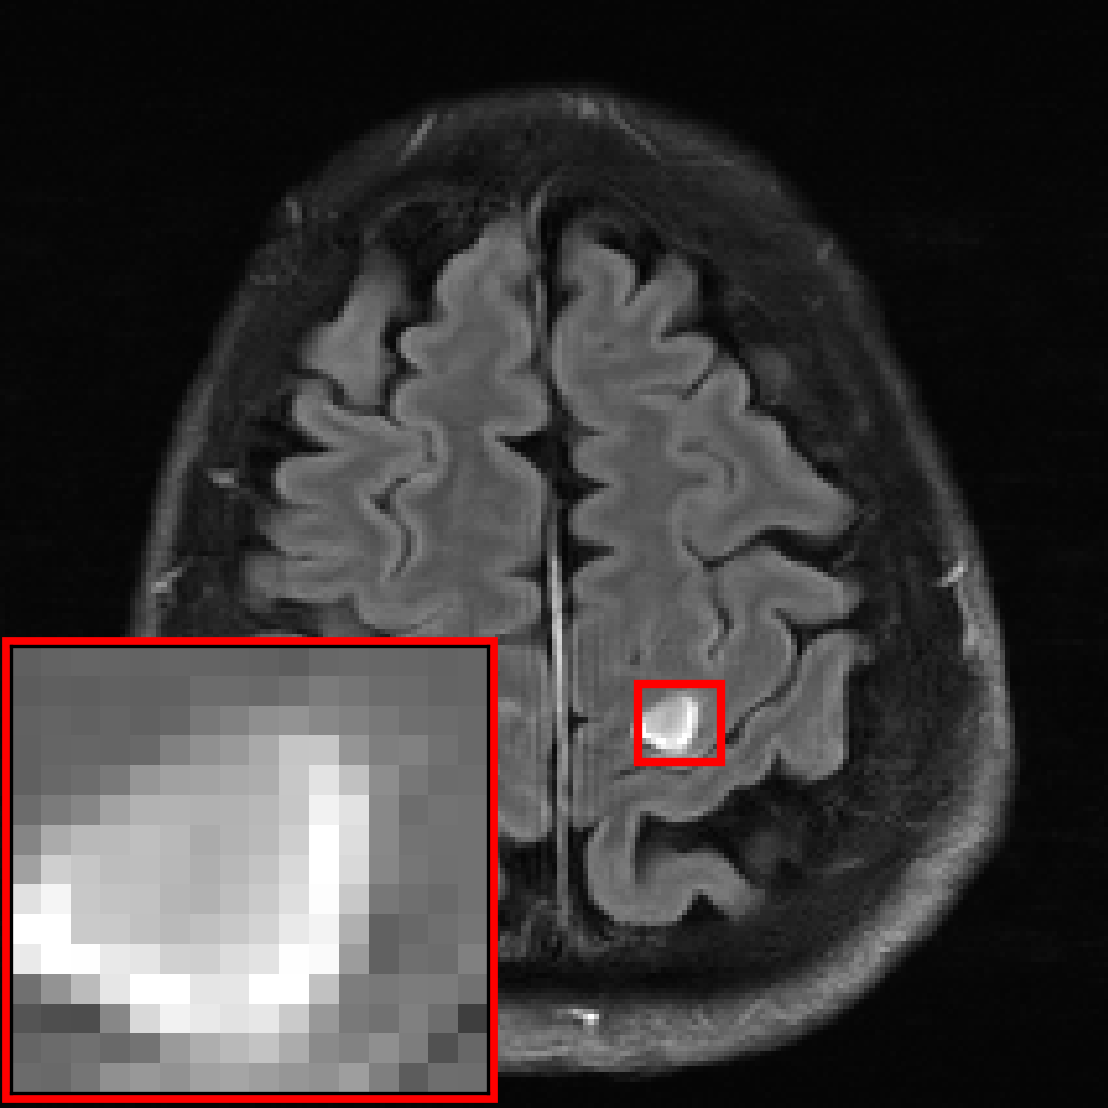

Many of our experiments are based on splits of the fastMRI dataset \citepzbontarFastMRIOpenDataset2019a, the most commonly used dataset for MRI reconstruction research. Figure 2 depicts samples from the fastMRI dataset and shows that MRI data vary in appearance across different anatomies and image contrasts (T1, T2, etc.). The image distribution also varies across vendors and magnetic field strengths of scanners, as the strength of the magnet impacts the signal-to-noise ratio (SNR), with stronger magnets leading to higher SNRs.

The fastMRI dataset stands out for its diversity and size, making it particularly well-suited for exploring how different data distributions can affect the performance of deep learning models for accelerated MRI. In our experiments in Section 3, 4, 5, and 6 we split the fastMRI dataset according to different attributes of the data. In Section 7, we showcase the generalizability of our findings on a diverse collection of 17 different datasets.

We consider two distributions and , and train U-nets \citepronnebergerUNetConvolutionalNetworks2015a, ViTs \citepdosovitskiyImageWorth16x162021b and end-to-end VarNets \citepsriramEndtoEndVariationalNetworks2020b on data from distributions and on data from distribution separately. We also train the same models on data from and , i.e., . We then evaluate on separate test sets from distribution and . We consider the end-to-end VarNet because it is a state-of-the-art model for accelerated MRI, and consider the U-net and ViT as popular baseline models. This diverse selection of architectures (unrolled, convolutional, transformer) aims to demonstrate that our qualitative results are independent of the specific architectural choice. We consider the following choices for and , which are subsets of the fastMRI dataset specified in Figure 2:

Anatomies. are knees scans collected with 6 different combinations of image contrasts and scanners and are the brain scans collected with 10 different combinations of image contrasts and scanners.

Contrasts. We select as PD-weighted knee images from 3 different scanners and are PDFS-weighted knee images from the same 3 scanners.

Magnetic field. Here, we pick to contain all 3.0T scanners and to contain all 1.5T scanners regardless of anatomy or image contrast.

We are given data from two distributions and , where distribution can be split up into sub-distributions . We consider the following choices for the two distributions, all based on the knee and brain fastMRI datasets illustrated in Figure 2:

Anatomy shift: is knee data collected with all 6 different combinations of image contrasts and scanners, and are the different brain datasets collected with 8 different combinations of image contrasts (FLAIR, T1, T1POST, T2) and scanners (Skyra, Prisma, Aera, Biograph mMR).

Contrast shift: are all FLAIR, T1POST, or T1 brain images and are T2 brain data.

Magnetic field shift: are brain and knee data collected with 1.5T scanners (Aera, Avanto) and are brain and knee data collected with 3T scanners (Skyra, Prisma, Biograph mMR).